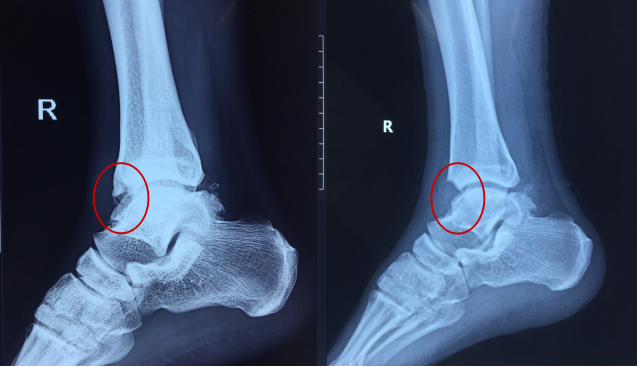

术前影像学检查

▲术前X片